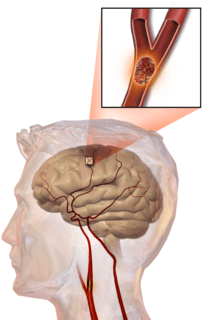

Illustration of an embolic stroke, showing a blockage lodged in a blood vessel.

In thrombotic stroke a thrombus[31] (blood clot) usually forms around atherosclerotic plaques. Since blockage of the artery is gradual, onset of symptomatic thrombotic strokes is slower than that of a hemorrhagic stroke. A thrombus itself (even if it does not completely block the blood vessel) can lead to an embolic stroke (see below) if the thrombus breaks off and travels in the bloodstream, at which point it is called an embolus. Two types of thrombosis can cause stroke: